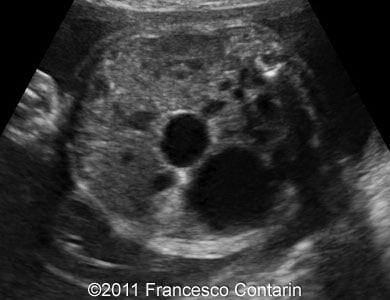

This is a case of a 24-year-old G3P2, with non contributive history, who was scanned at 32 weeks of gestation. Unilateral fetal multicystic kidney disease was found.

Images 1, 2, 3, and 4: The images show a series of longitudinal and transverse scans of the multicystic fetal kidney obtained at 32 weeks of pregnancy.